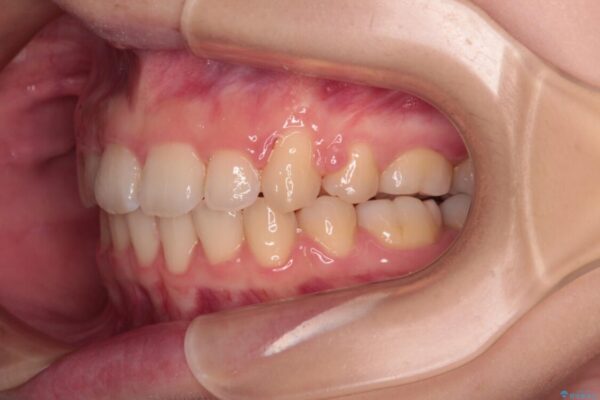

上下の前歯が突出しており、口が閉じにくいとのことで来院された患者様です。

上下前歯が著しく前突している状態であったので、上下左右の第1小臼歯4本を抜歯し、ワイヤー装置にて矯正治療を行うこととしました。

舌の突出癖により、前突になったと考えられたため、舌のトレーニングをしっかりと行うよう指導しました。

舌の突出癖があり、前歯の移動量も多くなるため、治療期間は長くなると予想されましたが、13ヶ月という予定の半分程度の期間で終えることができました。